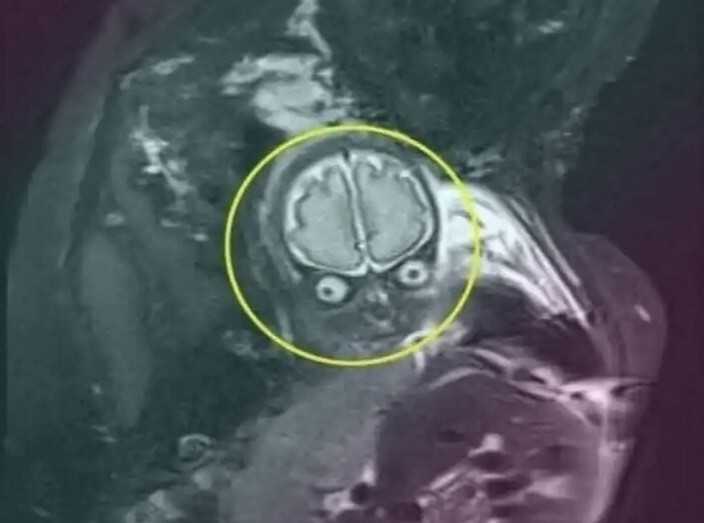

МРТ делают и беременным женщинам - разумеется, по медицинским показаниям. А вот снимки младенцев из утробы будущим мамам лучше не показывать. Во избежание.

Снимки с УЗИ принято сохранять как первые фото своих будущих детей. Зато эти изображения, сделанные при исследовании аппаратом МРТ, способны любого впечатлительного человека довести до икоты.